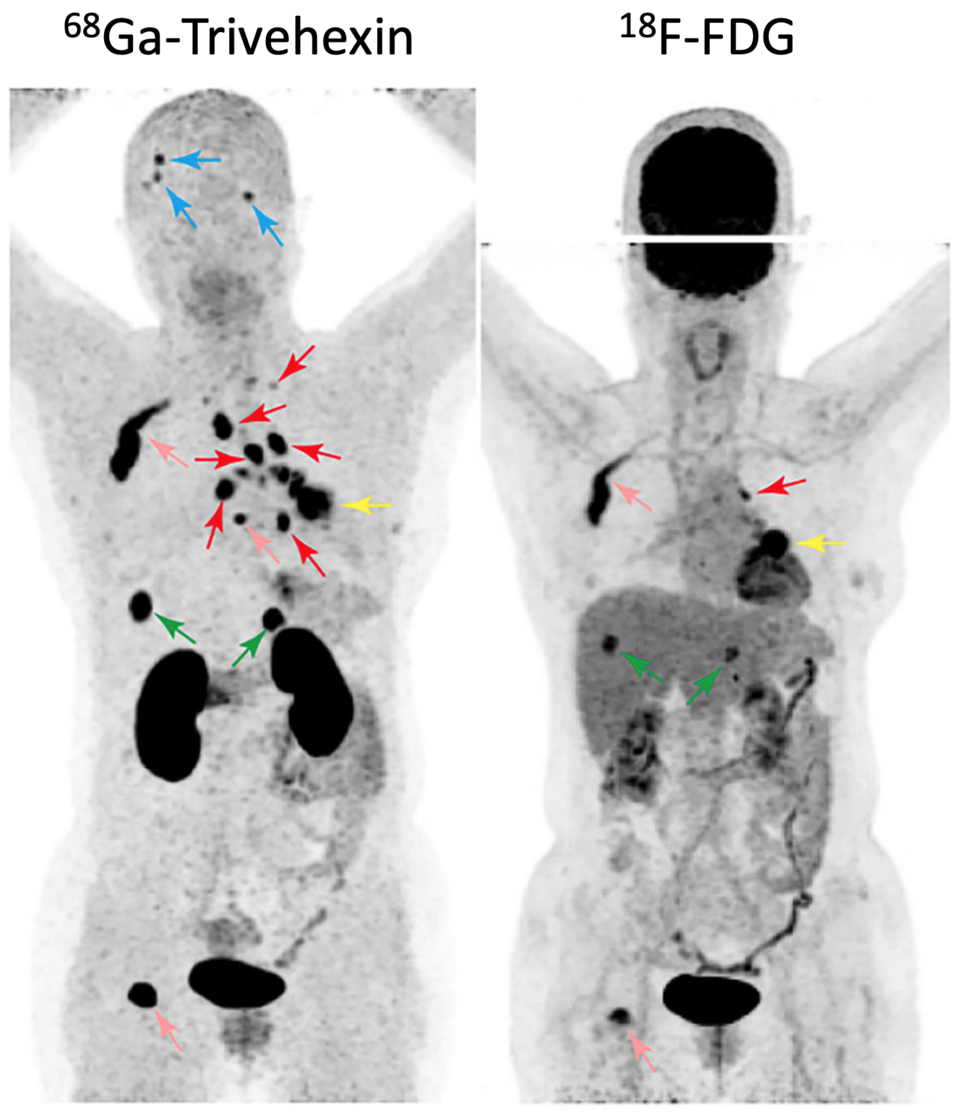

PET — NSCLC Ga-68 vs FDG Comparison

Comparison of Ga-68 Trivehexin and FDG PET imaging in non-small cell lung cancer evaluation

PET Downloaded 2026-03-15

Pet

Ga68

Wikimedia Commons: Ga-68-Trivehexin vs FDG Non Small Cell Lung Cancer Brain Metastases AdvSci 2025 He-et-al.png